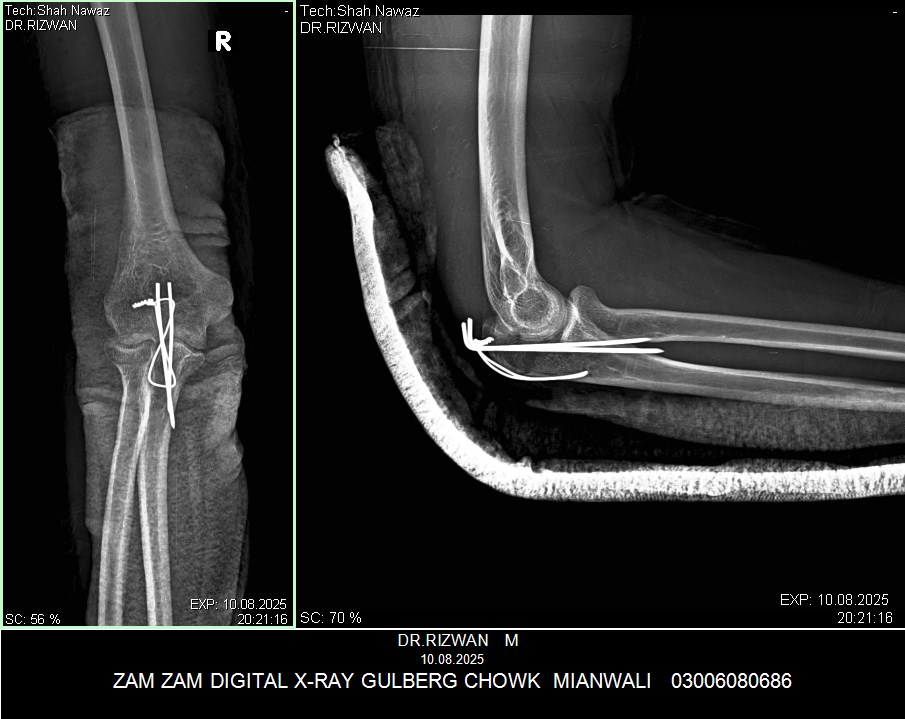

My husband had elbow surgery on 9th of August. I want to know about physiotherapy. When can we start physiotherapy so he can bend and extend his arm freely.Kindly guide us. If we start now will it effect joint or not. TIA

Attach Photo here: